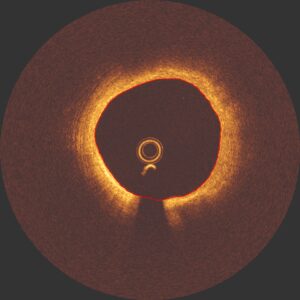

In the clinical report we describe the entire pullback: plaques, stents, minimal luminal area, particularities (like dissections, hematoma’s, thrombus, plaque ruptures) etc.

F.e: A and B show resp. concentric and eccentric fibro-fatty plaque, C shows concentric mixed plaque, fibrofatty and superficial calcium and D shows eccentric mixed plaque, fibro-fatty and superficial calcium with a plaque rupture.